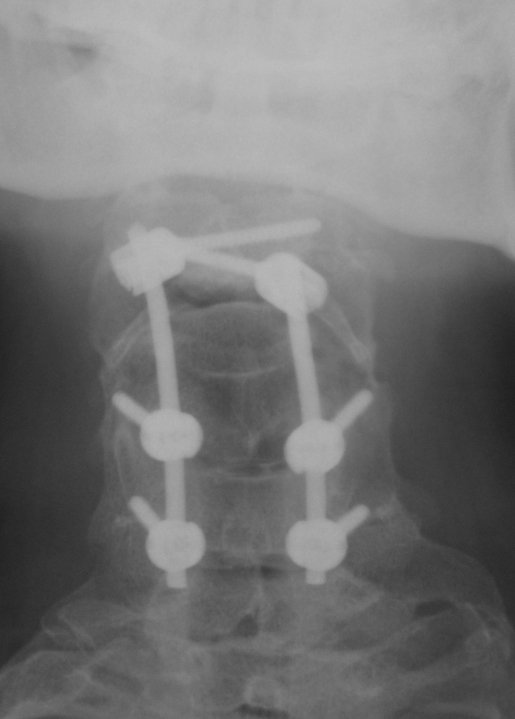

Klippel-Feil PostOp AP Grafisi Klippel-Feil PostOp Lateral Grafi Klippel-Feil Postop BT C2 Seviyesi

Resim 3: Postop direkt grafilerde C2-C6 seviyesindeki stabilizasyon sistemi görülmektedir. C2 seviyesinde intralaminar (en sağdaki resim), C5-C6 seviyelerinde lateral kitle vidaları kullanılmıştır.